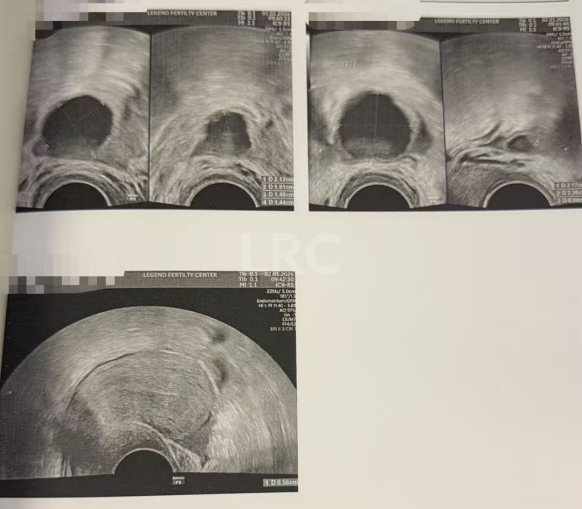

月经第二天 促排第一天

阴超检查:基础卵泡 3 颗

- 右侧卵泡 1 颗 (6mm)

- 左侧卵泡 2 颗 (7,5mm)

激素水平检查:

- 促黄体生成素 3.60 miu/ml

- 雌二醇 42.5 pg/ml

- 促卵泡生成素 10.60 miu/ml

- 泌乳素 25.10 miu/L

促排第三天

阴超检查(只数能用卵子):

- 右侧卵泡 2 颗 (9,4mm)

- 左侧卵泡 2 颗 (11,5mm)

- 促黄体生成素 6.00 miu/ml

促排第六天

阴超检查:

- 右侧卵泡 2 颗 (13,9mm)

- 左侧卵泡 2 颗 (17,7mm)

- 促黄体生成素 12.00 miu/ml

子宫内膜厚度:4.0 mm